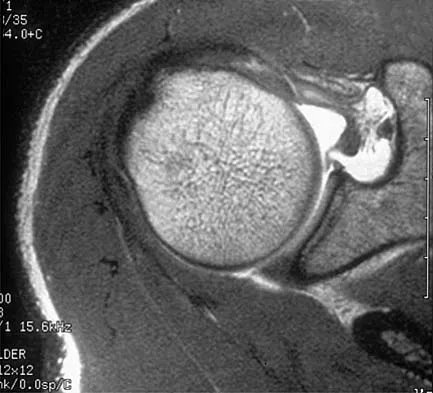

A patient has right shoulder pain. Figure 1a shows a gadolinium-enhanced transverse MRI scan at the level of the coracoid. Figure 1b shows an arthroscopic view of the anterior structures from a posterior portal. These images reveal which of the following findings?

The area shown in the arthroscopic view and MRI scan is referred to as a Buford complex and represents a normal labral variant. It consists of a thickened, cord-like middle glenohumeral ligament, a superior labral attachment of the middle glenohumeral ligament just anterior to the biceps tendon, and absence of the anterosuperior labrum. This combination of findings can be confusing and may simulate labral pathology. Mistaken repair of the lesion back to the glenoid rim can result in significant loss of external rotation. A Bankart lesion would be located at the inferior anterior glenoid rim. The subscapularis is seen anterior to the labrum. Normal variations that occur in the anterosuperior labrum can simulate pathology. Gusmer PB, Potter HG, Schatz JA, et al: Labral injuries: Accuracy of detection with unenhanced MR imaging of the shoulder. Radiology 1996;200:519-524. Griffin LY (ed): Orthopaedic Knowledge Update: Sports Medicine. Rosemont, IL, American Academy of Orthopaedic Surgeons, 1994, pp 47-63.

- Williams MM, Snyder SJ, Buford D Jr: The Buford complex: The "cord-like" middle glenohumeral ligament and absent anterosuperior labrum complex. A normal anatomic capsulolabral variant. Arthroscopy 1994;10:241-247.